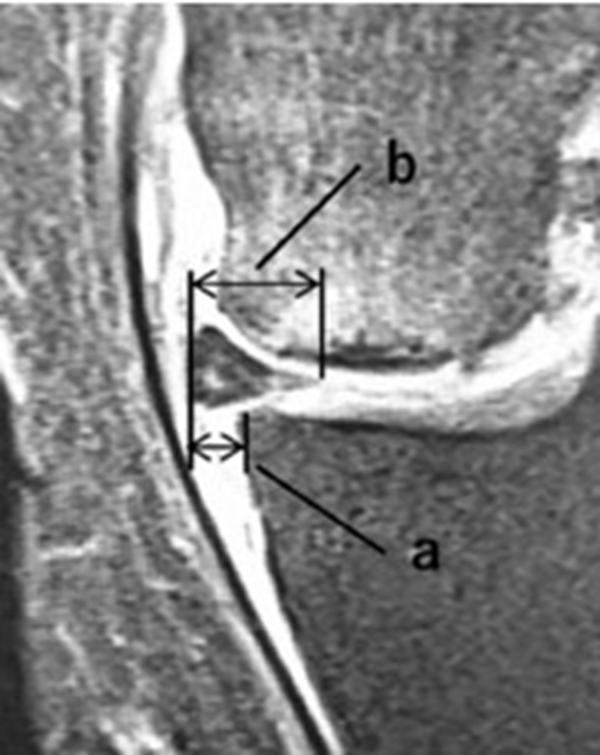

内侧半月板挤压(MME)以绝对值和挤压相对百分比 (RPE) 的形式呈现,其定义为挤压半月板宽度与整个半月板宽度相比的百分比

a.患者,59岁女性,AP侧位片显示SONKⅠ期,FTA<180°;b.MRI T2显示病变深度<20mm,患者出现症状1年后保守治疗;c.75岁女性,X线显示SONKⅠ期,FTA>180°;d. MRI T2显示病变深度>20mm,患者于症状出现后11周行手术治疗